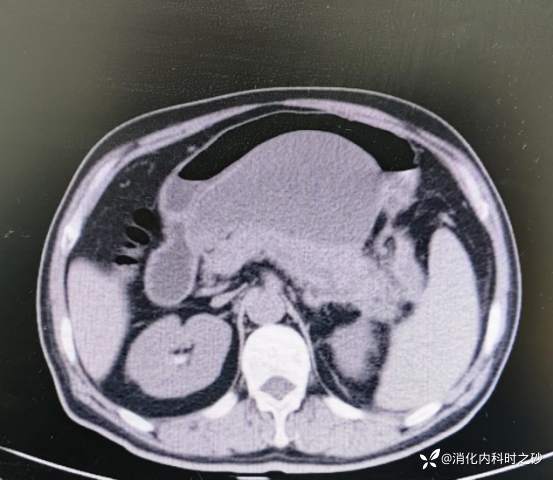

复查CT所见

CT示胰腺周围可见包裹性积液

腹部强化CT示已有胰腺假性囊肿形成

最大截面13.1cm×8.4cm的胰腺假性囊肿